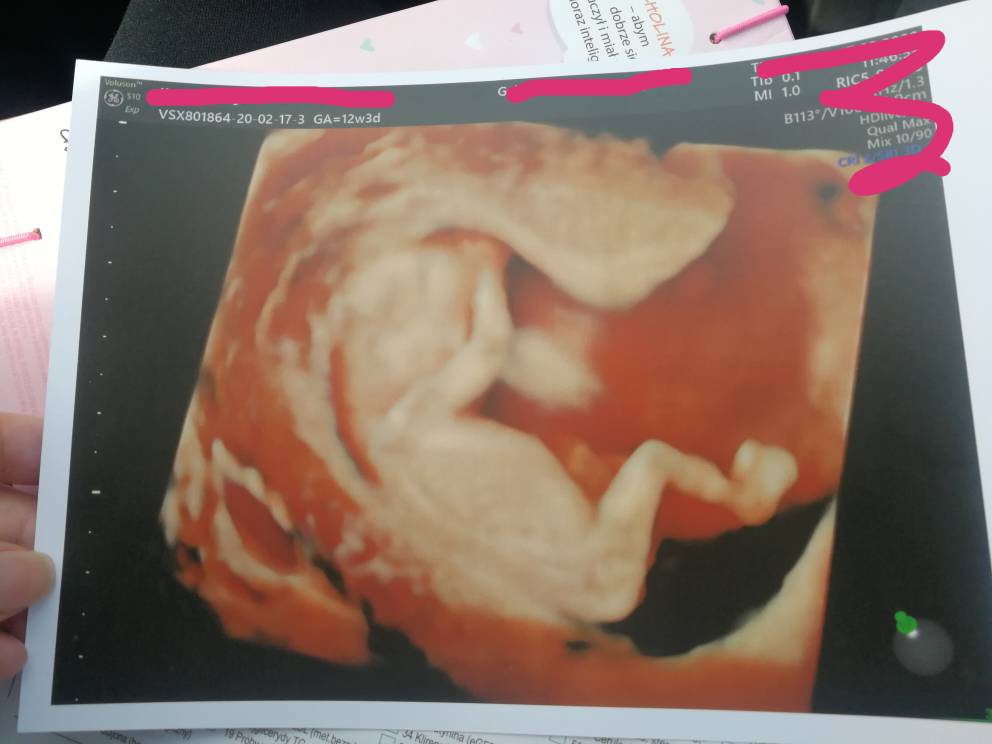

A to moje maleństwo z pn (12+3), dxidziol nie chciał współpracować.. Wykryto Arse, za 3 dni następne usg genetyczne.

Załączniki

• IMG_20200217_120347.jpeg

IMG_20200217_120347.jpeg

45,7 KB · Wyświetleń: 113

Błądząca tętnica prawa podobojczykowa... Ma to coś związane z przełykiem.. Być może z wada serduszka.. Tak naprawdę w internecie nic nie można konkretnego znaleźć, mam nadzieję że dowiem się w pn coś wiecej po kolejnym usg. Jest markerem zespołu downa też podobno... Chociaż u nas to jedyna nieprawidłowość. Trzymajcie kciuki